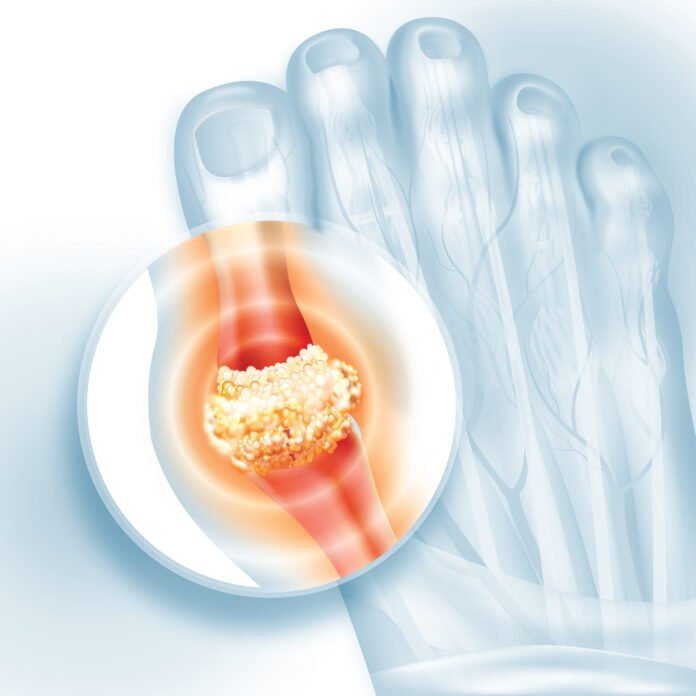

यूरिक एसिड शरीर का एक अपशिष्ट पदार्थ है. यह तब बनता है जब शरीर ‘प्यूरीन’ नाम के केमिकल को तोड़ता है, ये केमिकल हमारे भोजन में पाए जाते हैं. आमतौर पर, विशेषज्ञ बताते हैं कि यूरिक एसिड ब्लड फ्लो में घुल जाता है और किडनी द्वारा फिल्टर किया जाता है, जिसके बाद यह पेशाब के माध्यम से शरीर से बाहर निकल जाता है. हालांकि, विशेषज्ञ यह भी बताते हैं कि जब इसका लेवल बहुत ज्यादा बढ़ जाता है या जब किडनी इसे प्रभावी ढंग से बाहर निकालने में असमर्थ होते हैं, तब यूरिक एसिड शरीर के भीतर जमा होना शुरू हो जाता है. और बाद में, यह जोड़ों और ऊतकों के आसपास सुई जैसे क्रिस्टल बना लेता है, जिससे सूजन, दर्द और गठिया जैसी गंभीर समस्याएं उत्पन्न हो सकती हैं.

नेशनल इंस्टीट्यूट ऑफ हेल्थ के एक अध्ययन के अनुसार, अगर आपकी किडनी ठीक से काम नहीं कर रही हैं, तो समझ लें कि खून में यूरिक एसिड का स्तर बढ़ गया है. इस स्थिति को ‘हाइपरयूरिसीमिया’ कहा जाता है. यूरिक एसिड शरीर में कहीं भी जमा हो सकता है. लेकिन, विशेषज्ञ बताते हैं कि यह मुख्य रूप से जोड़ों और किडनी के आसपास जमा होता है. विशेषज्ञों का मानना है कि शरीर में यूरिक एसिड का बढ़ा हुआ लेवल हार्ट डिजीज, डायबिटीज और किडनी से जुड़ी समस्याओं का खतरा बढ़ा सकता है.

- हाइपरयूरिसीमिया से पीड़ित लोगों को अपने जोड़ों, पैरों और टांगों में सूजन और असहनीय दर्द का अनुभव होता है.

- कुछ लोगों को अपने पैरों के तलवों में जलन का भी अनुभव होता है. इसके अलावा, पैर के बड़े अंगूठे में भी दर्द हो सकता है.